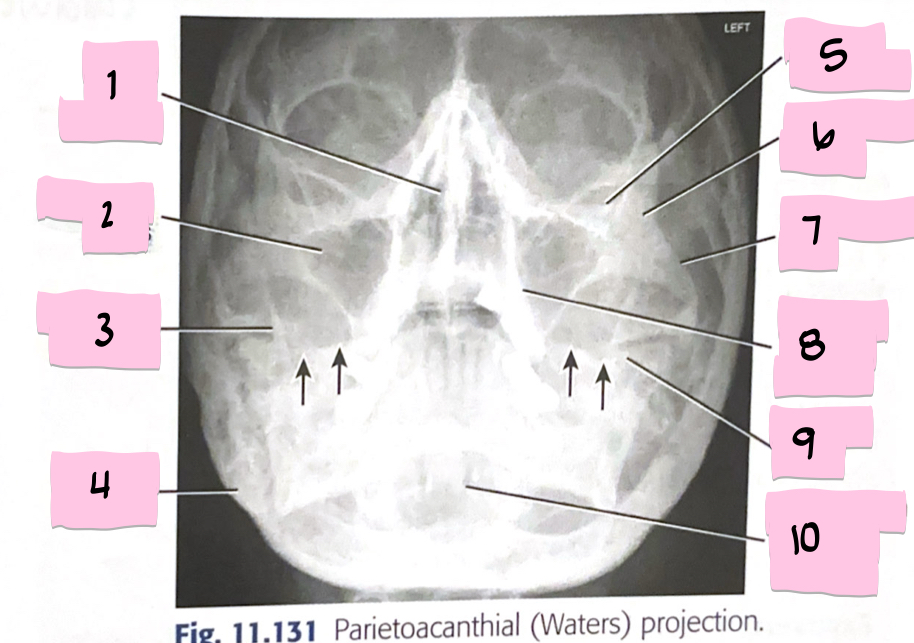

What is 1 pointing to?

Bony nasal septum

What is 2 pointing to?

Maxillary sinus

What is 3 pointing to?

Coronoid process

What is 4 pointing to?

Mastoid process

What is 5 pointing to?

Inferior orbital rim

What is 6 pointing to?

Zygomatic bone

What is 7 pointing to?

Zygomatic arch

What is 8 pointing to?

Maxillary alveolar process

What is 9 pointing to?

Petrous ridge

What is 10 pointing to?

Dens within foramen magnum